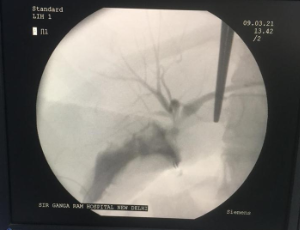

Bouveret’s syndrome is a rare condition characterized by gastric outlet obstruction from an ectopic gallstone, facilitated by aberrant connection of the biliary and luminal gastrointestinal tracts. Establishing a diagnosis of Bouveret’s syndrome can be aided by clinical, radiologic, and endoscopic assessments and importantly relies on prompt diagnosis and management. Despite its rarity, the disease confers a high rate of morbidity and mortality.